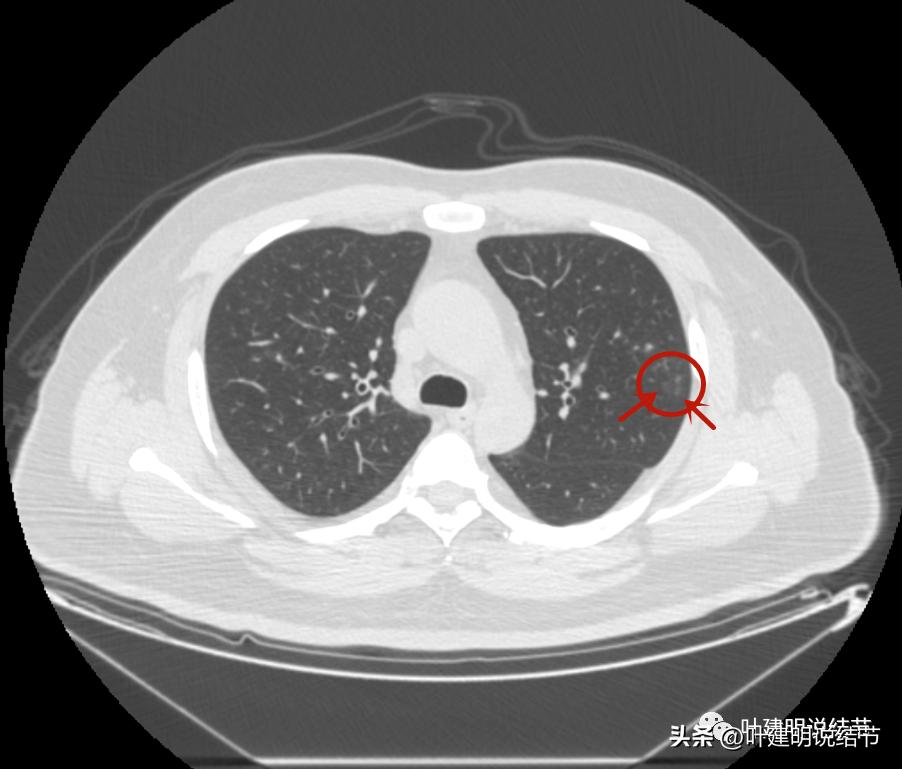

左上叶的病灶1、2、3都没有了!!!完全没有了!那当然说明是炎症性的,居然全部吸收了!

但左上病灶4仍在,形态也没有明显变化,无好转,也无明显进展。这是肿瘤性质的吗?虽然存在2年多了,但因为它的兄弟们都不见了,让我对它认定的肿瘤范畴也产生了怀疑,也许是纤维增生而已呢!

右上叶倒又出现了新的病灶:

右上病灶1:是新出现的,密度甚低,但轮廓较清,不典型增生吗?

右上病灶2:新出现的,整体轮廓较清,但感觉较散在,不致密,也不是圆形或类圆形,大概是炎性的吧!